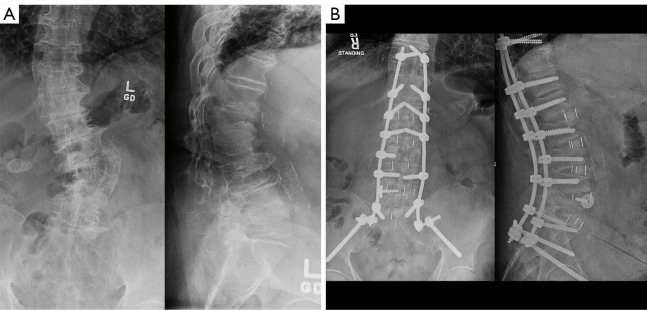

Abstract Image